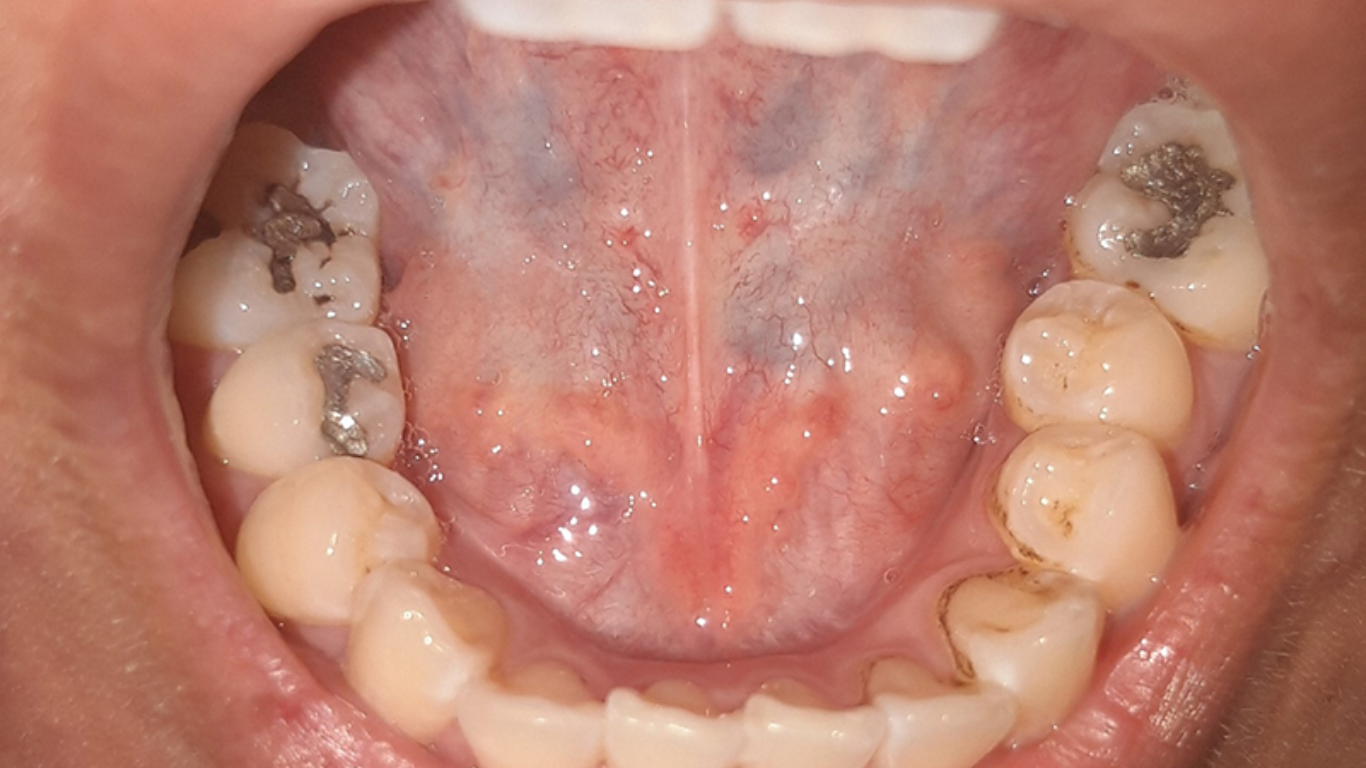

HPV ở khoang miệng thường không bộc lộ triệu chứng rõ ràng, khiến nhiều người chủ quan và bỏ qua. Dấu hiệu nhiễm HPV ở miệng có thể bao gồm nốt sần, mụn cóc, mảng đỏ hoặc trắng trên môi, lưỡi, khoang miệng. Tổn thương thường không đau, có thể trơn hoặc sần sùi như súp lơ, đôi khi mọc thành chùm. Nếu xuất hiện triệu chứng này, cần đi khám chuyên khoa để chẩn đoán sớm.

- Những nốt sần bất thường: Một trong các dấu hiệu nhiễm hpv ở miệng là sự xuất hiện của các mụn nhỏ, mọc riêng lẻ hoặc kết thành từng cụm giống như mụn cóc. Chúng có thể có màu trắng, hồng, đỏ hoặc tiệp với màu niêm mạc miệng.

- Mụn trong khoang miệng: Các nốt mụn này có thể xuất hiện ở bất kỳ vị trí nào, nhưng thường thấy ở lưỡi, vòm miệng, nướu hoặc môi.

- Không đau nhưng đáng lo: Điểm đặc trưng của những tổn thương do HPV là chúng thường không gây đau, phát triển chậm và có bề mặt nhẵn hoặc chai cứng.